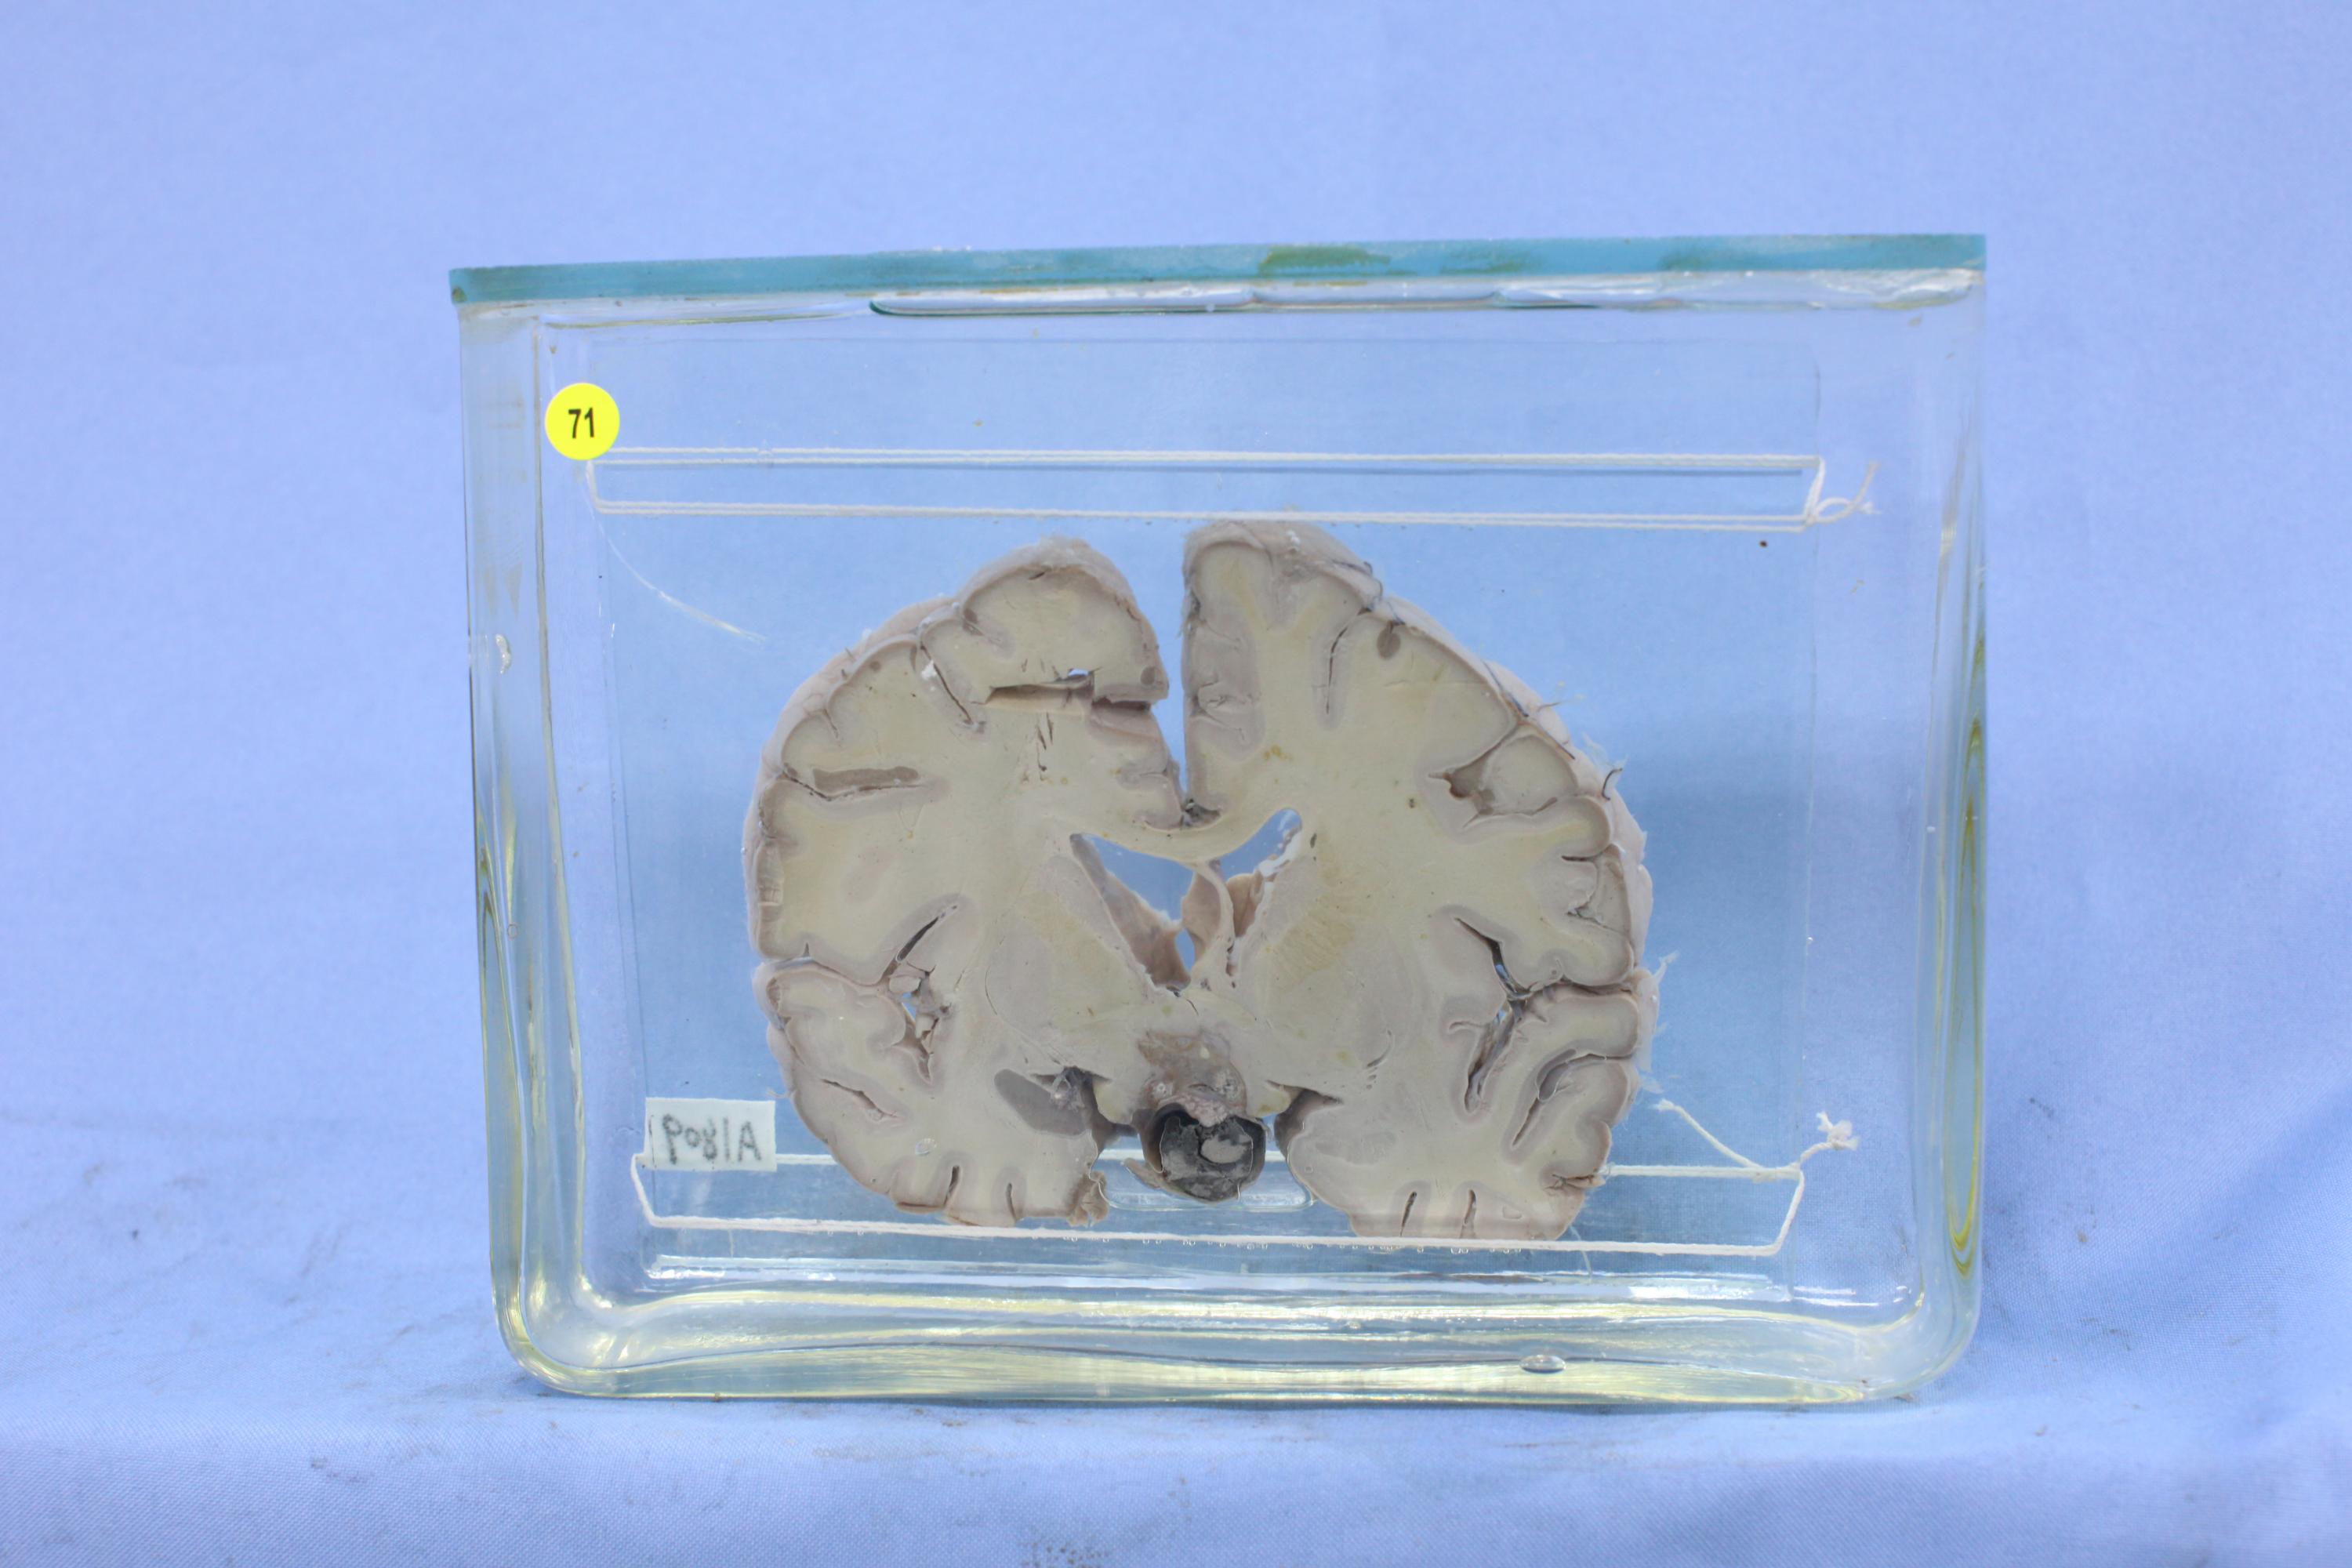

神经疾病-65-71. 恶性垂体瘤侵犯下丘脑

大脑经基底节冠切,垂体部位见直径1cm的黑色出血灶,其中可见灰红色细胞成分,并向上浸润前联合以下部位,其中可见灶状坏死。